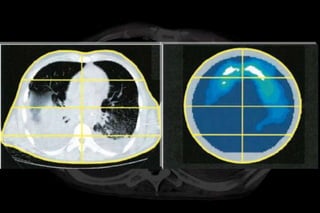

CRF   Insuflação total

Análise de multipla regressão para variações locais de impendância

durante insuflação lenta (standard electrode positioning) quando

projetado sobre mudanças sincronizadas nas imagens de TC de tórax.

Análise de multiplaregressão para variações locais de impendância durante insuflação lenta (standard electrode positioning) quando projetado sobre mudanças sincronizadas nas imagens de TC de tórax.